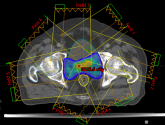

(1)、病例展示一:巨块型肝细胞肝癌合并门静脉癌栓

确诊肝癌并治疗后4月余复诊,伴有高热。腹部核磁:肝右叶异常强化灶,考虑肿瘤性病变;门静脉右支及门静脉主干管腔内见低密度影填充,考虑栓子形成。

病理诊断:肝细胞肝癌。治疗方案:碳离子放疗,总剂量:PTV:70Gy(RBE)/10Fx。同步治疗:阿替利珠单抗注射液+甲磺酸仑伐替尼胶囊。

影像学对比